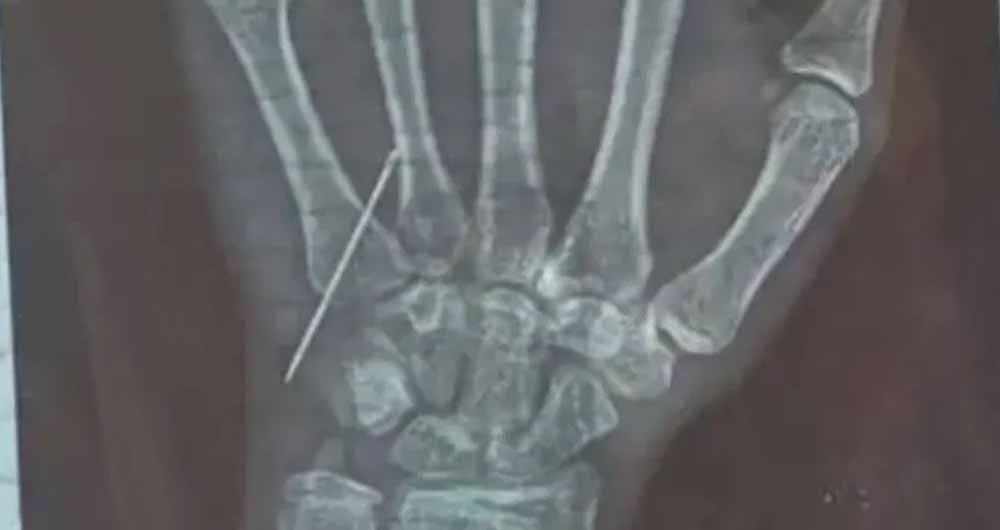

रंजना की तबीयत खराब होने पर परिवार वाले उसे लेकर हाटा स्थित एक अस्पताल में गए। वहां एक कर्मचारी ने बाएं हाथ में इंजेक्शन लगाया, लेकिन तुरंत ही रंजना को असहनीय दर्द शुरू हो गया। थोड़ी देर बाद दूसरे हाथ में भी इंजेक्शन लगाया गया, मगर आराम नहीं मिला। रातभर दर्द से कराहती बच्ची को परिजन दोबारा अस्पताल ले गए, लेकिन वहां से सिर्फ दवा देकर वापस भेज दिया गया। दर्द बढ़ने पर एक्स-रे करवाया गया, जिसमें खुलासा हुआ कि निडिल टूटकर नस में फंसी हुई है।

न्याय न मिलने पर पीड़ित परिवार ने जिलाधिकारी कार्यालय में गुहार लगाई, जिसके बाद DM गोरखपुर ने सीएमओ को तत्काल कार्रवाई के निर्देश दिए। बच्ची को जिला अस्पताल में भर्ती कराया गया, जहां डॉक्टरों ने 2 दिन इलाज के बाद सफल ऑपरेशन कर नस में फंसी निडिल निकाल दी।